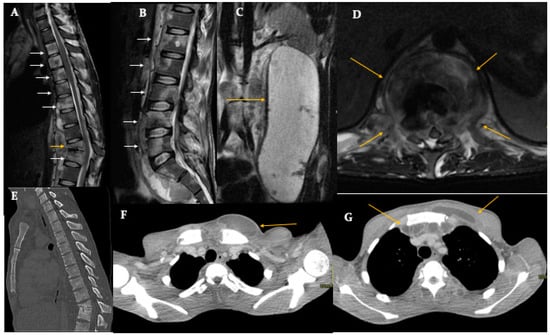

5. Tuberculous Origin (Pott’s Disease)